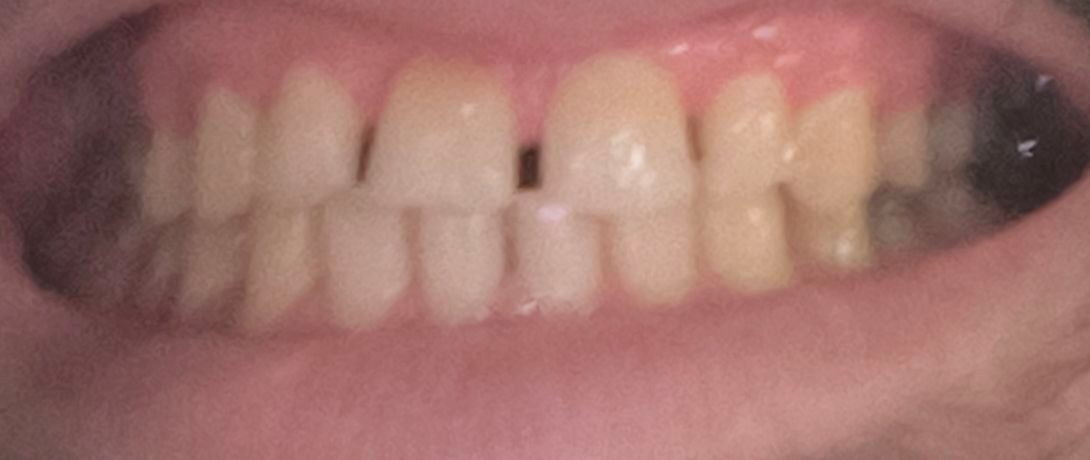

Аноны, добрый вечер.

Посоветуйте пасту зубную после пломбирования и чистки от камня передних зубов.

Спасибо.

Аноним 06/08/25 Срд 05:38:29 1634925 25

Ска, весь рот в гное, будто бы стоматит, сходил к зубным феям - сказали все збс с корнями зубов и ни одного намёка на кариес где-либо, хотя начиналось всё будто бы флюс и самый пиздец около одного зуба, прописали онли антибиотики, но самое очко , что болезненность ещё и в области мягких тканей подбородка, который и отдает в этот самый пиздец при надавливании - даже будто бы второй подбородок чуть-чуть присутствует, температура и общая слабость, есть риск флегмоны? пиздец за шо(

Аноним 06/08/25 Срд 10:08:53 1634947 26

Как профиль лица меняется после удаления восьмерок? В инете нашел только фотки до/после у женщин, и вроде как челюга уменьшается. У мужиков так же? После удаления не получится больше моггать челюхой омежек?

Аноним 07/08/25 Чтв 13:36:06 1635134 27

>>1634947

>Как профиль лица меняется после удаления восьмерок